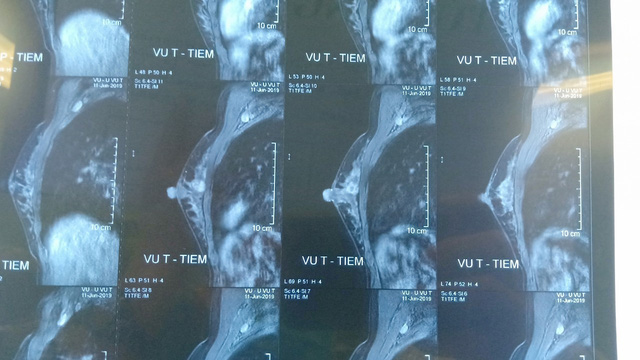

Hình ảnh phim chụp khối u của bệnh nhân trước khi phẫu thuật

Bị sốc khi phát hiện ung thư vú giai đoạn 2 khi mới tuổi 29, chị Đ. T. T. (ở Văn Giang, Hưng Yên) là một trong số bệnh nhân phát hiện ung thư vú (UTV) khi tuổi còn rất trẻ. Theo lời kể của bệnh nhân, chị vô tình sờ thấy khối u ở vùng ngực, đến bệnh viện để thăm khám thì được chẩn đoán bị UTV giai đoạn 2. ThS.BS Vũ Anh Tuấn - Khoa Phẫu thuật lồng ngực và mạch máu, bệnh viện Bạch Mai chia sẻ, sau khi phẫu thuật ổn định về, bệnh nhân sẽ bắt đầu phác đồ điều trị hóa chất. Sau một năm, các bác sĩ sẽ đánh giá tình trạng toàn thân xem có tổn thương ung thư tái phát ở bất cứ vị trí nào trên cơ thể thì sẽ có thể thực hiện phẫu thuật tái tạo hình thể vú cho bệnh nhân.